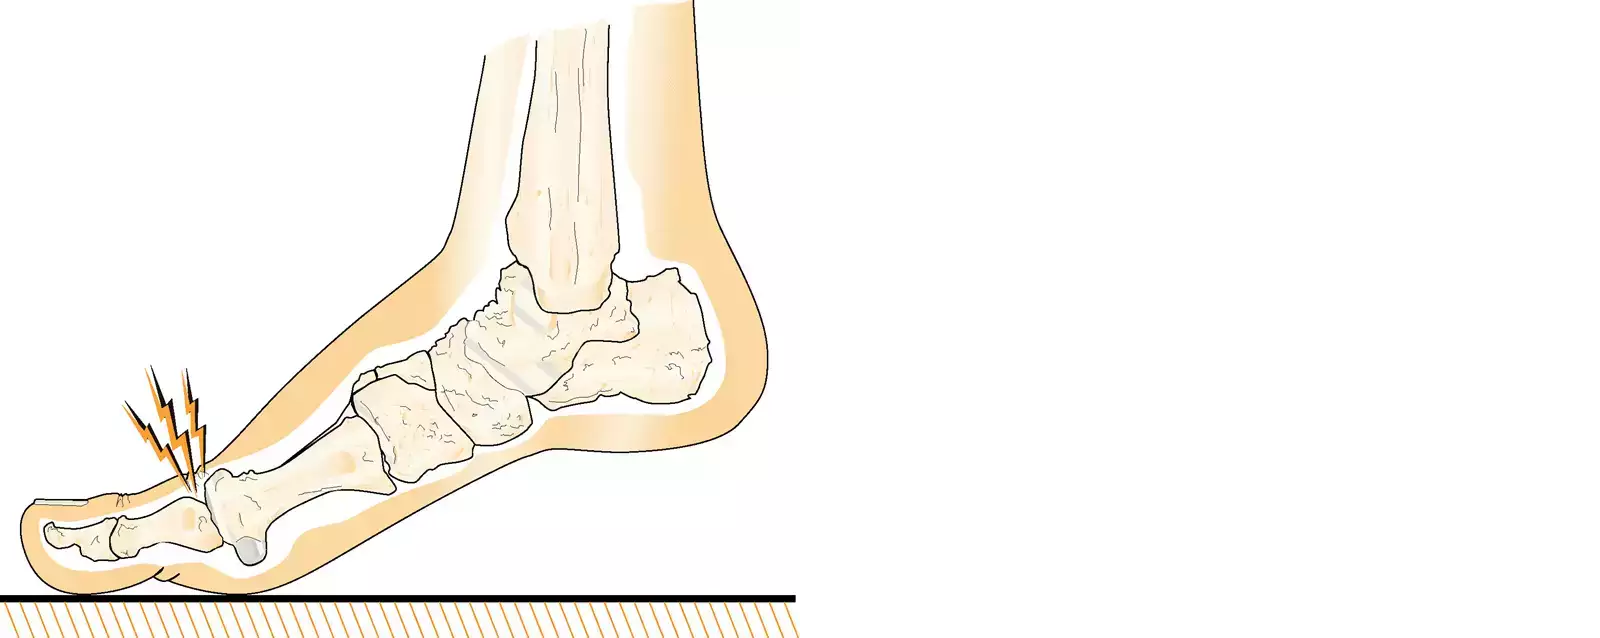

Hallux rigidus kännetecknas av smärta och nedsatt rörlighet i stortåns grundled. Symtomen förekommer ofta bilateralt och genesen är multifaktoriell.

Orsaken till hallux rigidus är huvudsakligen artros i stortåns grundled. [3][4][5]

Hallux rigidus kan uppstå som en komplikation till hallux valgus eller som en komplikation efter trauma. Andra riskfaktorer för att utveckla hallux rigidus är hereditet, kvinnligt kön och artritsjukdomar så som reumatoid artrit och giktartrit.

Symtom

Symtom från stortåns grundled som talar för hallux rigidus är [6][7]

- stelhet och nedsatt rörlighet

- smärta vid belastning och rörelse

- tryckbesvär från skor

- ändrat gångmönster till följd av stelhet och smärta

- vilovärk

- distalt känselbortfall.